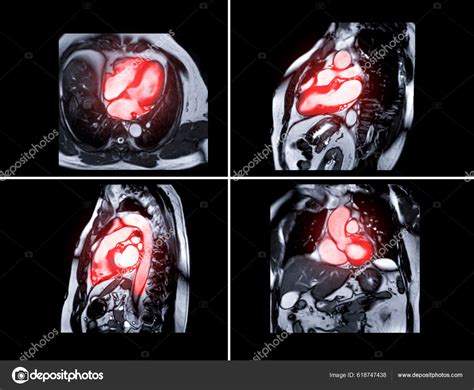

There are different types of MRI sequences used in cardiac imaging, each providing specific information:

• Cine MRI: This sequence captures moving images of the heart, allowing cardiologists to assess heart function and blood flow.

• T1-weighted and T2-weighted images: These sequences help identify tissue characteristics, such as inflammation or scarring.

• Contrast-enhanced MRI: By injecting a contrast agent, cardiologists can enhance the visibility of certain structures and detect abnormalities more effectively.